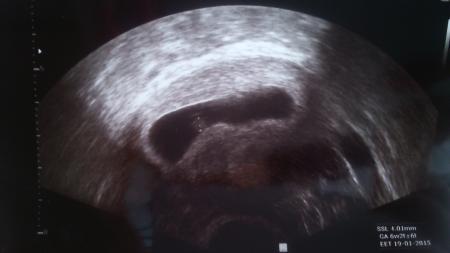

hallo, ich hatte heute meinen 2 ultraschalltermin...leider oder zum glück sah man eine fruchthöhle mit baby mit einer ssl von 4,01 mm...da ich aber vor 2 wochen schon einen us termin hatte, bei der die fruchthöhle zwar noch leer, aber 10 mm groß war und ich vor 3 1/2 wochen bereits positiv getestet habe, sollte ich eigentlich in der 8 ssw sein. wurde jetzt aber auf die 7 ssw zurückgesetzt und die ärztin meinte, das passt alles nicht zu meiner letzten regel und zu der fruchtöhle von vor 2 wochen. muss jetzt dienstag wieder hin um zu schauen ob es eine weiterentwicklung gab und man das herz schlagen hört...ansonsten ist es ein abort...ich hab so angst und weiß nicht was ich glauben und denken soll...das ist meine zweite ssw und meine erste endete auch mit einer fehlgeburt...

Vielen dank für eure aufbauenden Worte und es tut mir unheimlich leid Baby.2013 was dir passiert ist...das ist schlimm und ich bewundere dich, dass du die Hoffnung nicht aufgegeben hast. Ich tue mir unheimlich schwer damit positiv zu bleiben, weil ich das schon einmal erlebt habe mit einem missed abort. Diese Ungewissheit ist echt das Schlimmste! Weiß nicht wie ich die Tage bis Dienstag überbrücken soll und du hast Recht, sie hätte mir zumindest Blut abnehmen können. Denkt ihr es macht Sinn, wenn ich Freitag nocheinmal zu einem anderen Arzt gehe?! Ich habe das Bild des heutigen Ultraschalls beigefügt...